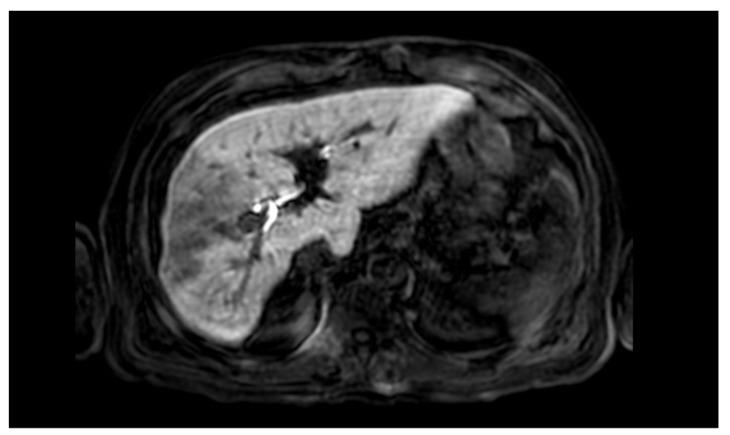

A 66-year-old Caucasian man with a history of Hepatitis C Virus (HCV) related liver cirrhosis and previous hepatocellular carcinoma of the VI segment treated with percutaneous ethanol infusion (PEI) seven years before presented to our clinics. A new nodular hypoechoic lesion in the VI hepatic segment was demonstrated on follow-up ultrasound examination. A hepatospecific magnetic resonance imaging (MRI) scan confirmed also the presence of a 18 × 13 mm nodular lesion in the V hepatic segment with satellite micronodules associated with V-VIII sectoral portal branch thrombosis. The case was then discussed at the multidisciplinary team meeting, and it was decided to perform a right hepatectomy. The postoperative course was regular and uneventful, and the discharge occurred seven days after the surgery. At eight-month follow-up, there was no clinical nor radiological evidence of neoplastic recurrence, with well-preserved liver function (Child-Pugh A5).

一名66岁的白种男性,有丙型肝炎病毒(HCV)相关肝硬化病史,7年前曾因VI段肝细胞癌接受过经皮乙醇注射(PEI)治疗,前来我们诊所就诊。随访超声检查发现VI肝段有一个新的结节性低回声病变。肝脏特异性磁共振成像(MRI)扫描也证实V肝段存在一个18×13mm的结节性病变,伴有卫星微结节,与V - VIII段门静脉分支血栓形成有关。然后在多学科团队会议上讨论了该病例,决定进行右半肝切除术。术后过程顺利,术后7天出院。在8个月的随访中,没有肿瘤复发的临床或影像学证据,肝功能良好(Child - Pugh A5)。